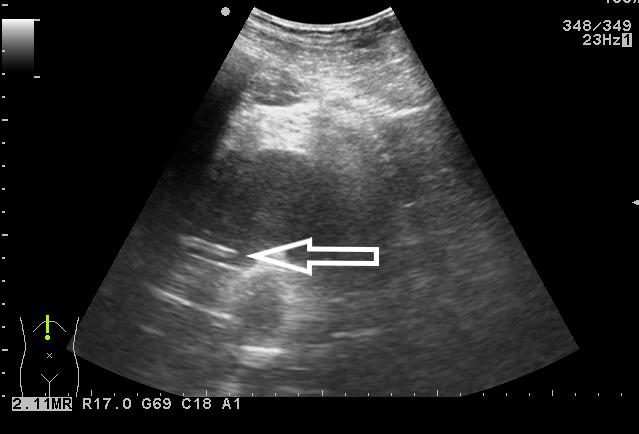

患者取俯卧位,充分暴露手术野,经臀超声扫查了解骶前脓肿情况,确定穿刺点,设计好穿刺路径。常规消毒铺巾,局麻,无菌保护套隔离探头。超声引导下PTC针穿刺直至脓腔边缘,迅速突破囊壁进入脓腔中心(图 3),退出针芯,外接注射器抽吸,见脓液流出(图 4)。将导丝通过针管插入脓腔,固定导丝,拔出针管,刀片沿导丝在臀部做2~3 mm小切口。插入扩张管扩张针道,经导丝将猪尾导管联合支撑管插入脓腔,超声确认穿刺到位(图 5)。拔出导丝,试抽有脓液流出,前推猪尾导管至其前端带侧孔段全部进入脓腔,拔出支撑管,可见液体流出。拉紧导管末端细线使导管尾端呈环状并固定,再次超声检查确定引流管在脓腔内(图 6),用缝线将引流管固定于皮肤上(图 7)。抽出约120 mL脓性液体,生理盐水反复冲洗脓腔,外接无菌引流袋。抽出的脓液取样送细菌培养,并做药物敏感实验。

| 图 3 超声引导下PTC针破壁进入脓腔 |

| 图 4 试抽出脓液 |